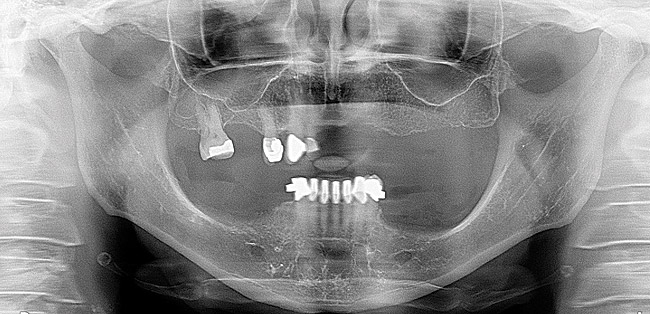

After a clinical examination was performed including diagnostic digital radiographs (Figure 2), diagnostic study models, photographs, and a CBCT scan, treatment options were discussed and the patient’s future expectations were addressed and documented. She had received a previous treatment plan and had been told she needed a sinus lift and a bone augmentation but decided against them. Her desire was to have a fixed solution so she would not have to remove her denture teeth.

A radiograph was taken to verify that the provisional with temporary sleeves was adapted perfectly to the shoulder of the multi-unit abutment as this prosthesis was used as the verification jig (Figure 7). The composite implant plug was removed to gain access to the multi-unit abutment screws that were then removed. Twenty-millimeter guide pins were inserted through the provisional. The patient could not close her mouth at this point.

Figure 7  A postoperative panoramic radiograph showing implant placement.

Figure 7